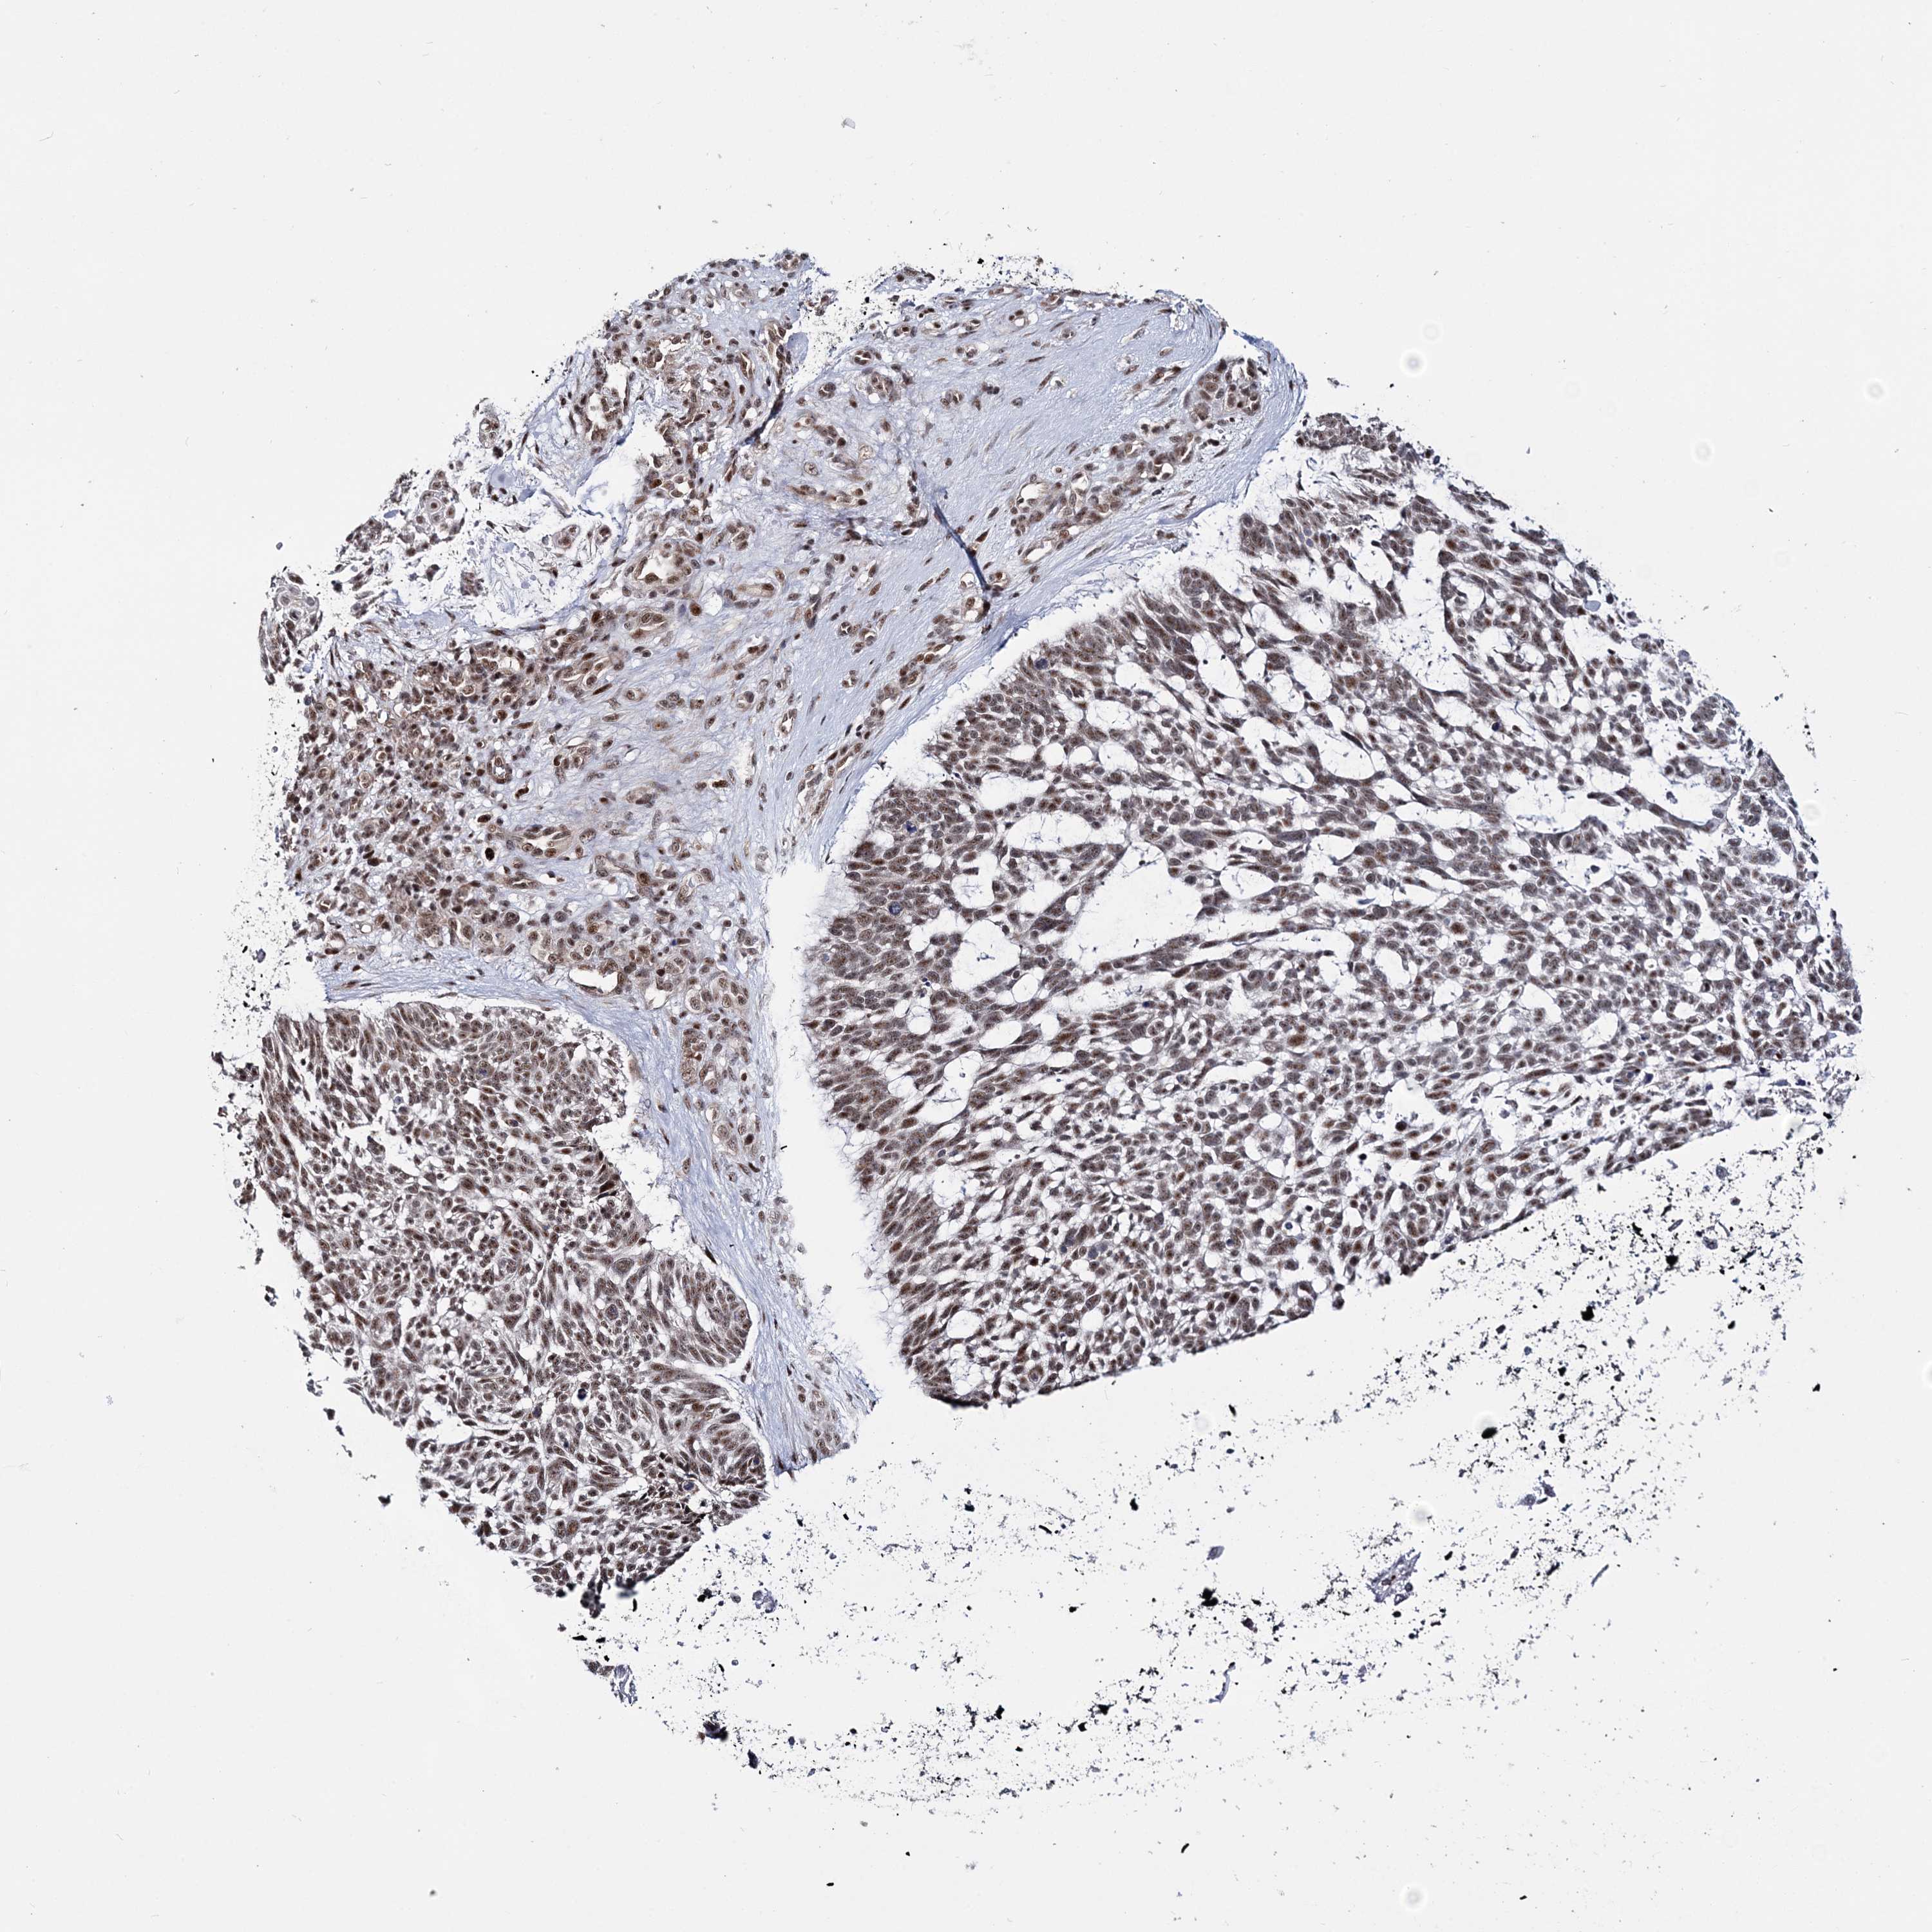

SKIN CANCER - Protein expressioni

A mouse-over function shows sample information and annotation data. Click on an image to view it in a full screen mode. Samples can be filtered based on level of antibody staining by selecting one or several of the following categories: high, medium, low and not detected. The assay and annotation is described here.

Antibody staining in the annotated cell types in the current human tissue is reported as not detected, low, medium, or high, based on conventional immunohistochemistry profiling in selected tissues. This score is based on the combination of the staining intensity and fraction of stained cells.

Each image is clickable and will lead to virtual microscopy that enables deeper exploration of all samples and also displays staining intensity scores, fraction scores and subcellular localization as well as patient and tissue information for each sample.

Antibody HPA036822

Staining

High

Intensity

Strong

Quantity

>75%

Location

Nuclear

Squamous cell carcinoma, NOS